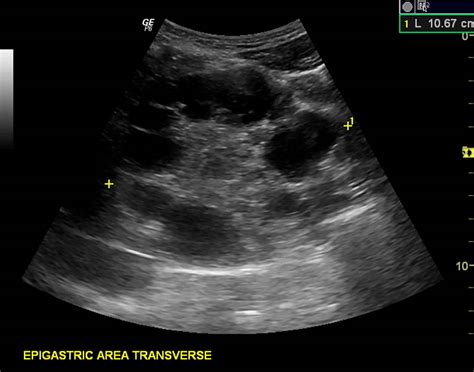

A liver ultrasound cyst is a fluid-filled sac that develops within the liver. These cysts can vary in size and number and are often discovered incidentally during routine imaging tests. Liver cysts can be classified into two main types: simple cysts and complex cysts. Simple cysts are benign and typically do not cause symptoms, while complex cysts may require further investigation due to the potential for malignancy.

The diagnosis of liver ultrasound cysts typically involves a combination of imaging tests and clinical evaluation. The primary diagnostic tool is the liver ultrasound, which provides detailed images of the liver and surrounding tissues. Additional tests may include:

• hepatic cyst ultrasound images

• simple cyst liver ultrasound